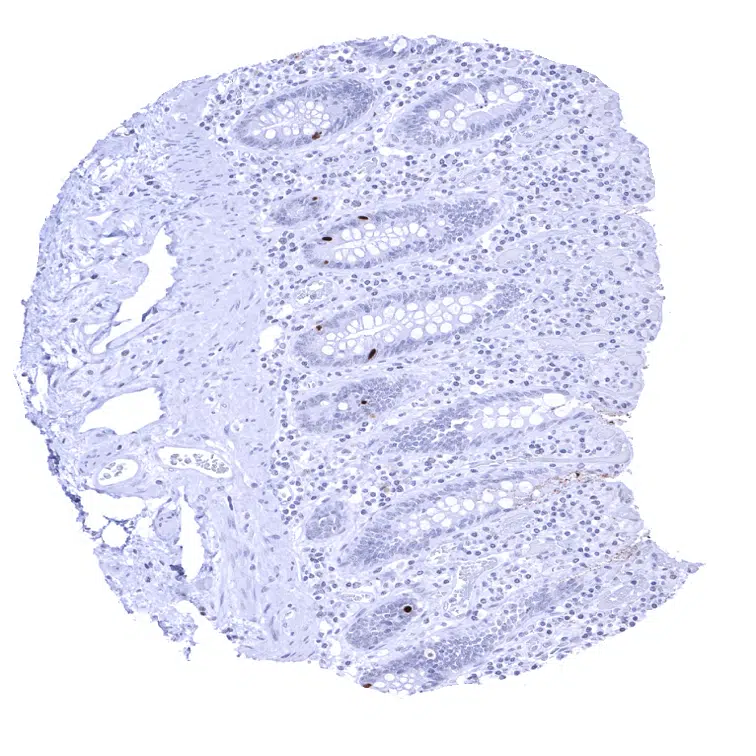

Rectum, mucosa – Moderate INSM1 positivity in few neuroendocrine cells of the rectal mucosa.